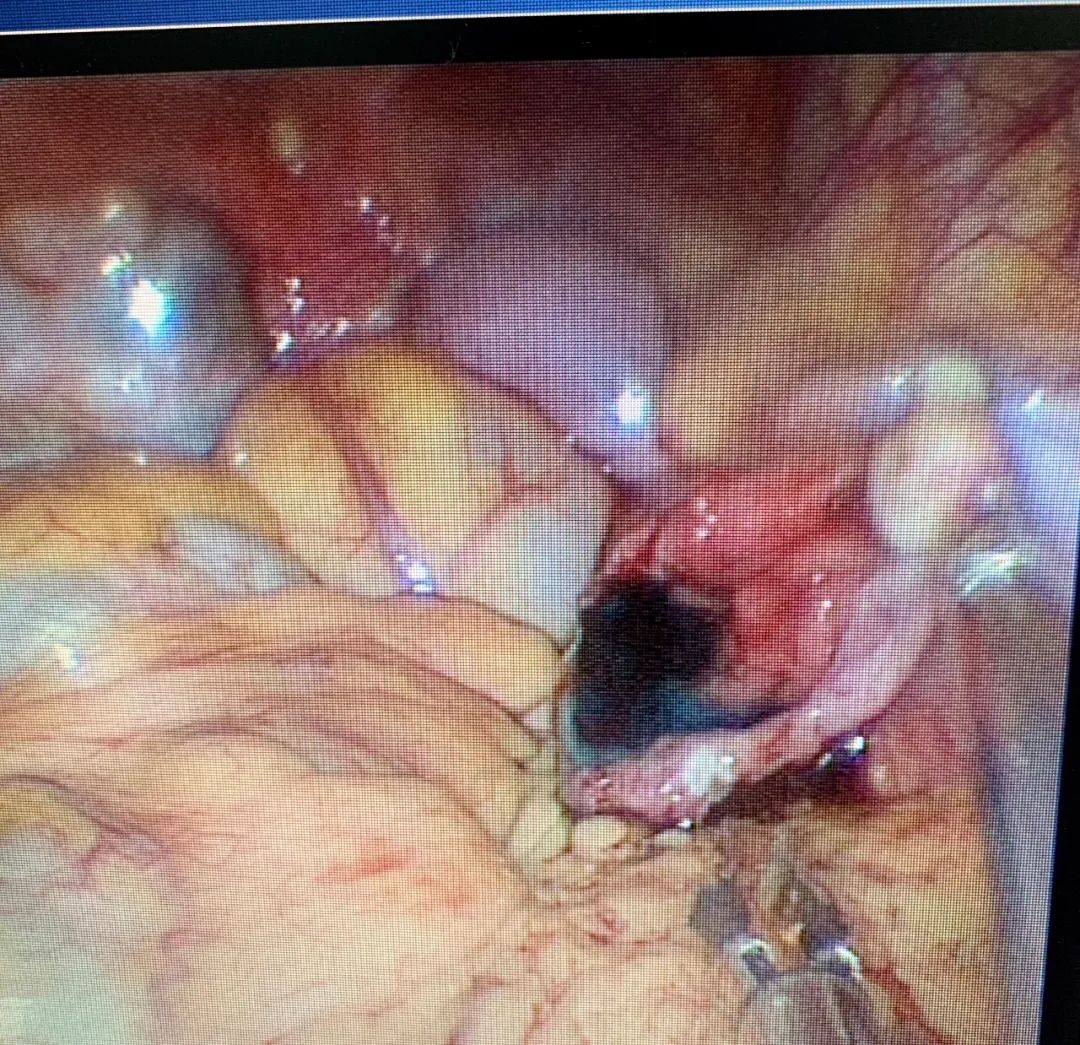

剪开末端组织,扩大切口,仅见少许伞粘膜。轻电凝末端浆膜层,使造口边缘外翻。双侧输卵管均疏通,成型良好。

LESS:双侧输卵管造口、疏通、成型